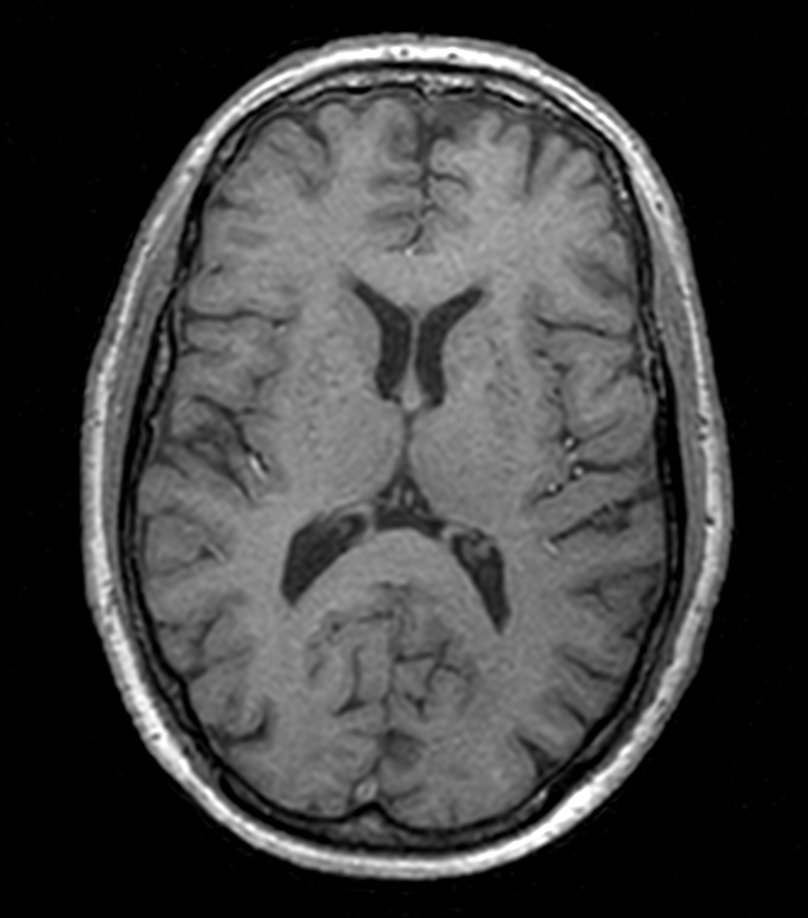

Axial 3D T1w TFE